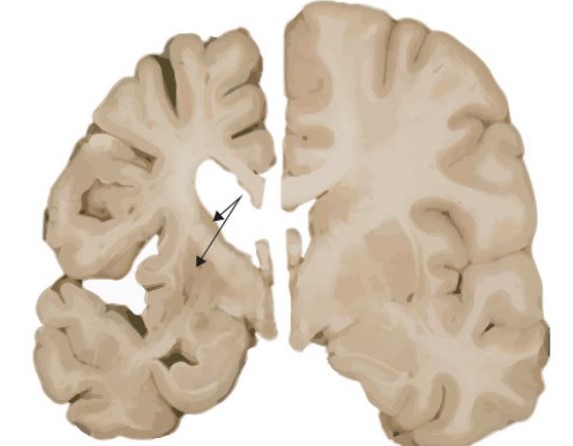

이러한 과도한 반복은 비정상적인 헌팅틴 단백질을 생성하며, 이 단백질은 뇌의 특정 신경세포에 손상을 입혀 점차적으로 죽음을 초래합니다.

헌팅턴병의 증상은 크게 운동, 인지, 정서 장애로 나눌 수 있습니다.

운동 장애 : 불수의적인 움직임 (클로레아): 몸이나 얼굴의 갑작스런, 빠르고, 불규칙한 움직임.

조정 장애 : 걷기, 균형 유지, 정교한 운동 수행에 어려움. 근육의 강직과 운동 둔화.